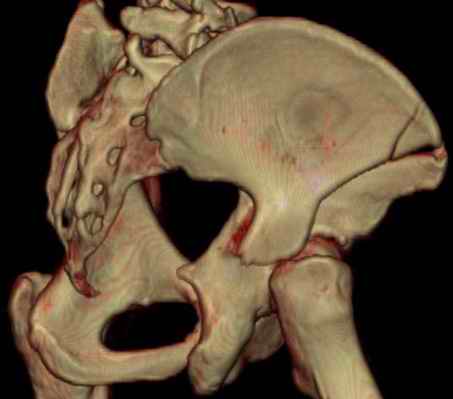

Посылаю схемы и 3D реконструкцию подобного повреждения. Называется он полным высоким двухколонным переломом вертлужной впадины, а "переломы крыла и тела подвздошной кости" входят в это понятие.

прикладываю схему доступа и случай.